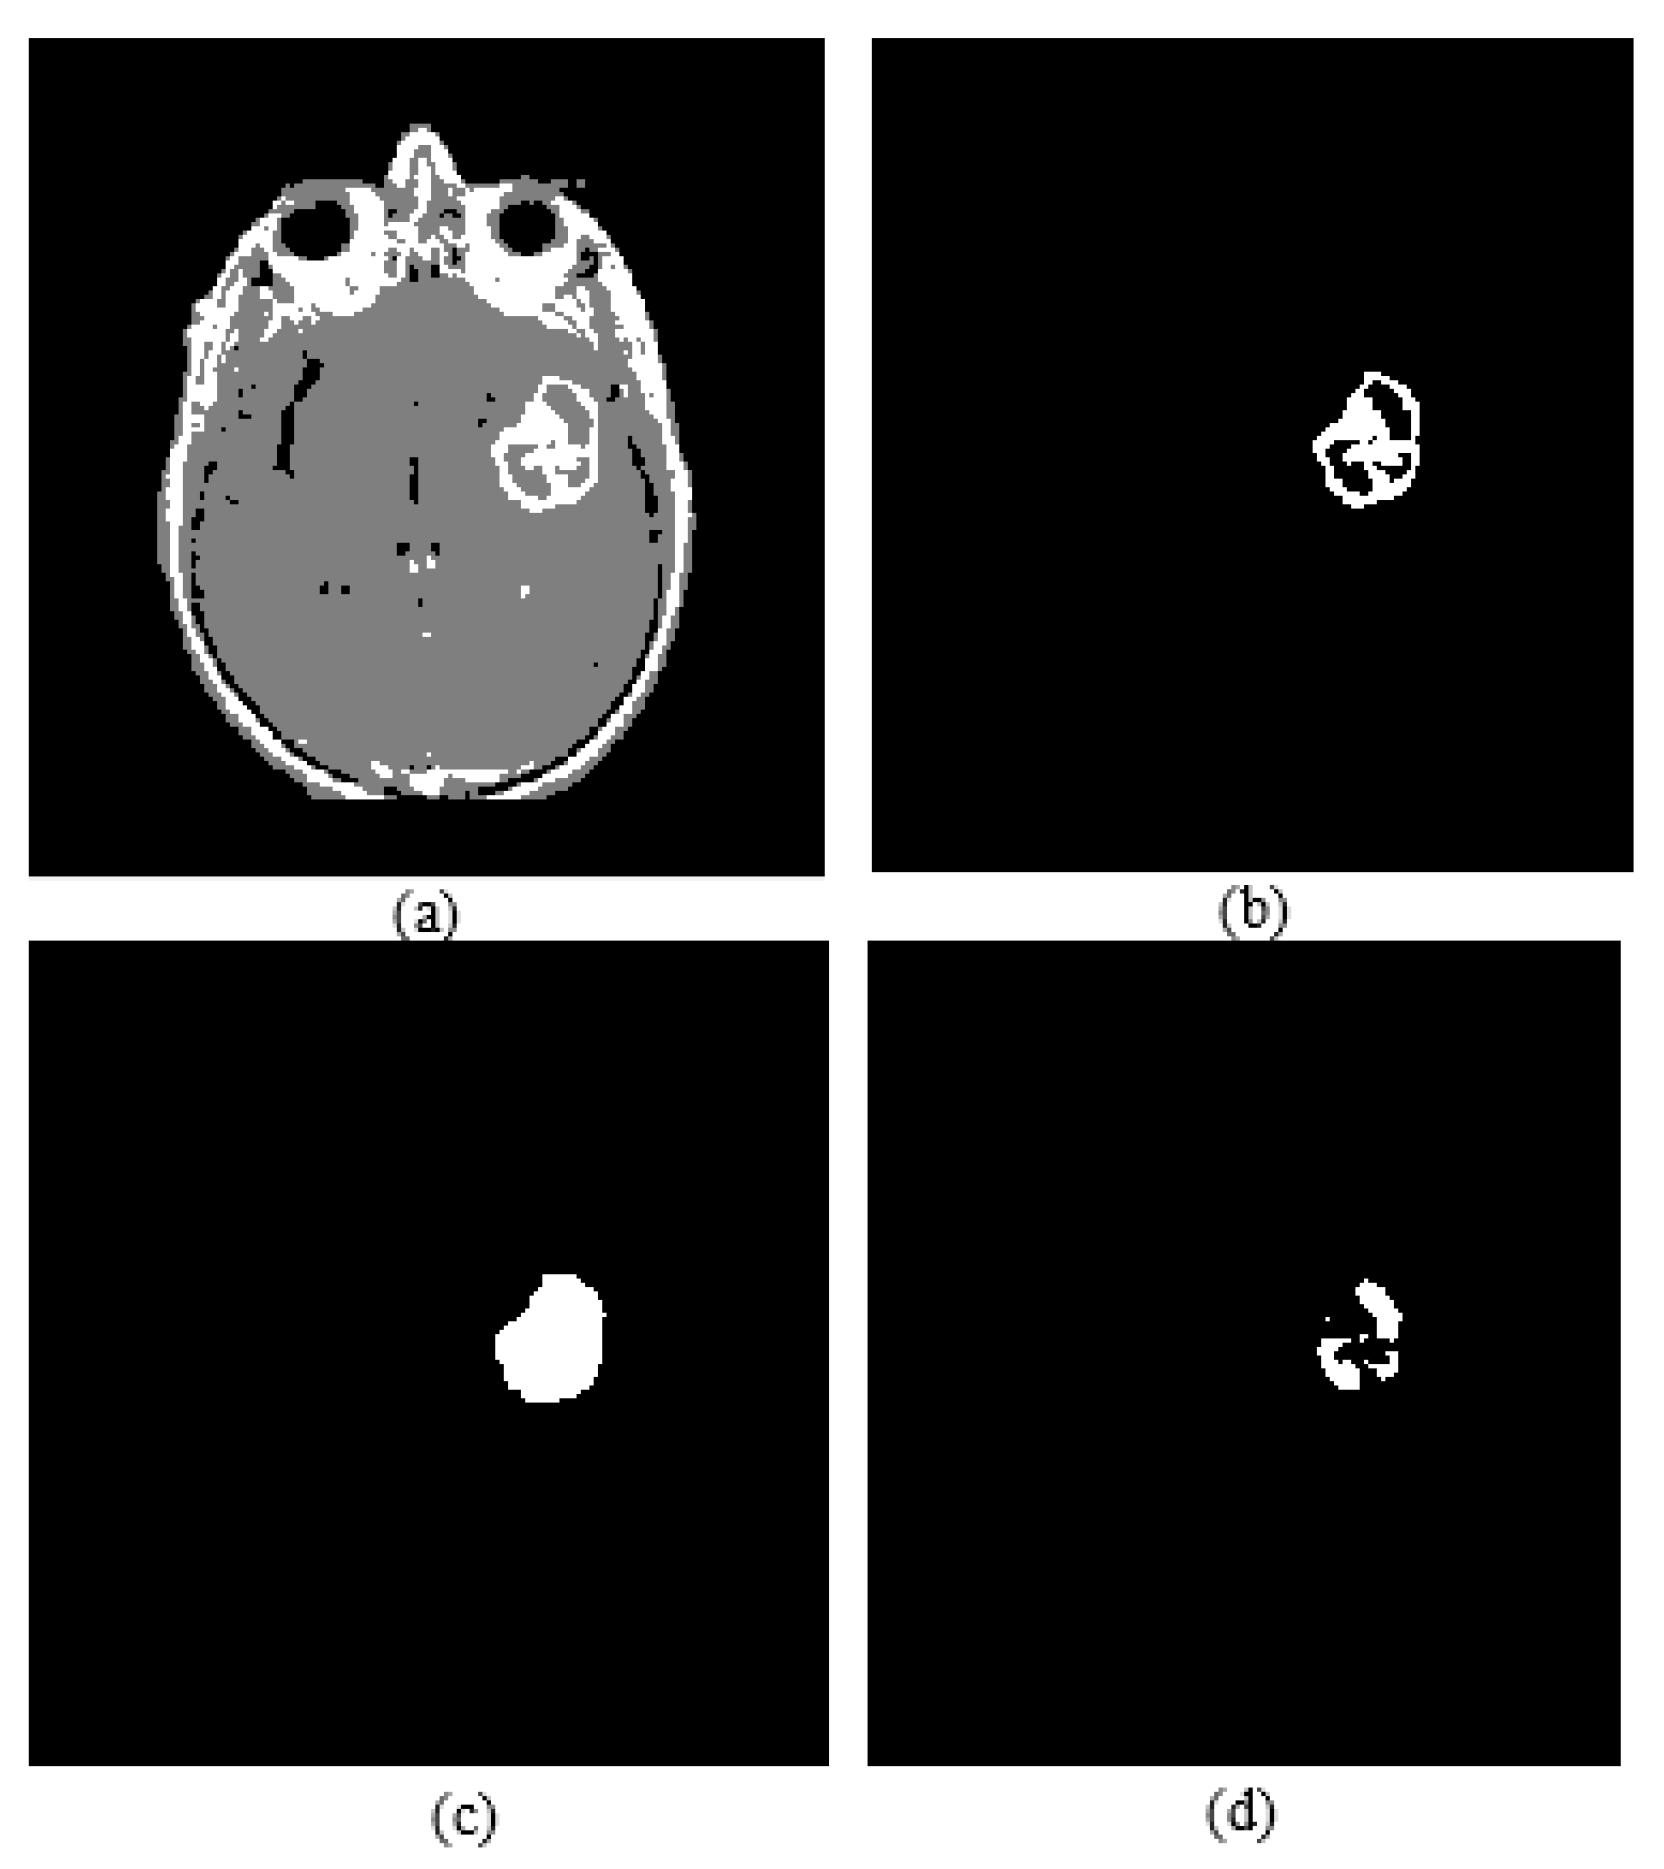

2.4. Active Core Segmentation and Volume Estimation

Active core segmentation and the volume estimation stage involve masking and FCM clustering operations, as outlined in Figure 11. The T1C image is converted to a binary image via FCM and a morphological opening operation (Figure 12c), and then skull stripping and whole tumor masks (Figure 12d,e) are applied on this image to obtain the enhancing/active core (Figure 12f). To obtain the necrotic/cystic core, a morphological closing operation is applied on the active core region (Figure 13c), then the active core is subtracted from this image (Figure 13d).

Figure 13.

(a) FCM clustering result of a T1C image; (b) enhancing tumor; (c) image closing result; (d) necrotic core.